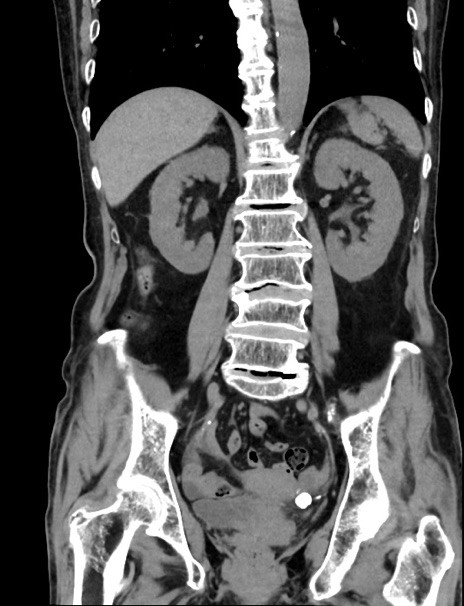

症例33(冠状断像)

【症例】70歳代 女性

【主訴】心窩部痛

【現病歴】延髄病変の精査・加療にて神経内科入院中。本日より心窩部痛あり。

【身体所見】右下腹部を中心に圧痛と反跳痛あり。

【データ】WBC 10900、CRP 0.02